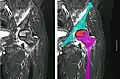

Nuclear magnetic resonance of avascular necrosis of left femoral head. Man of 45 years with AIDS. -